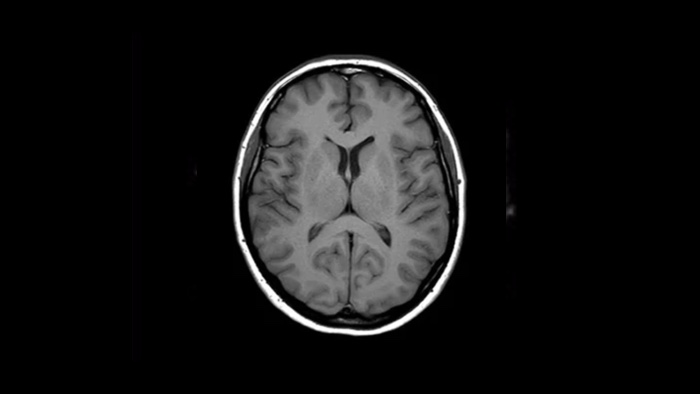

Ahora puede tenerlo todo con Ingenia Ambition. Ofrece la oportunidad de mejorar sus imágenes de resonancia magnética en todos los niveles.

Confianza diagnóstica Ofrece una resolución espacial hasta un 60% más alta en el mismo tiempo de escaneo. 4

Confianza diagnóstica Amplíe su capacidad de obtener imágenes excelentes en todas las áreas clínicas. Vea cómo se benefician sus compañeros.

Un salto en la confianza de la resonancia magnética pediátrica en Altona Children's Hospital.